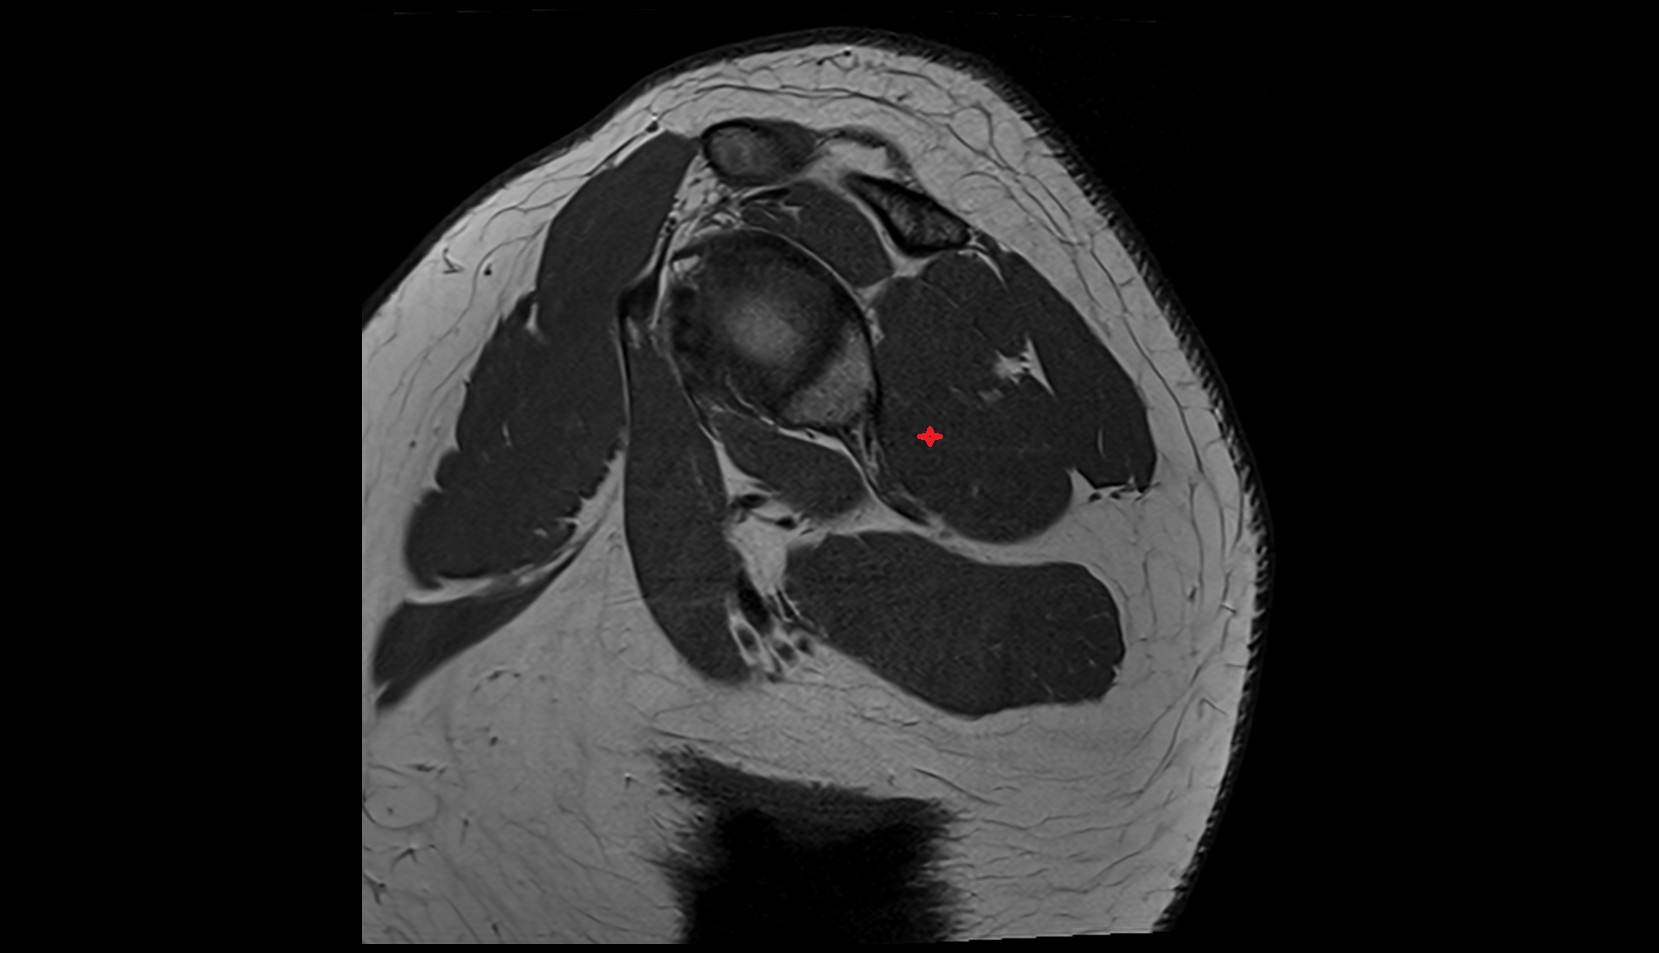

- Meniscus cartilage

- Medial meniscus

- Lateral meniscus

- Knee Joint